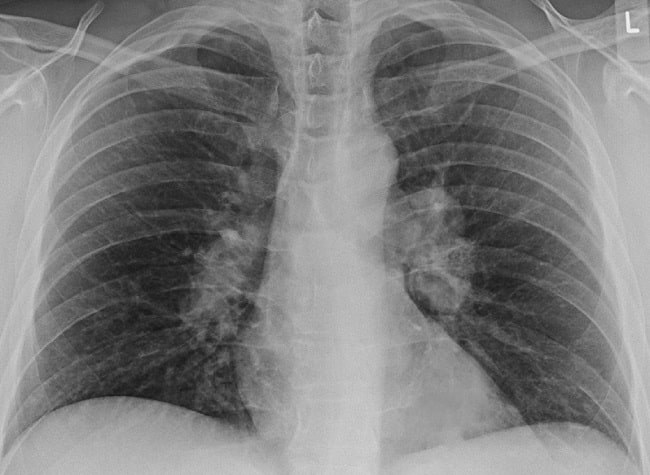

Proses penegakan sarkoidosis umumnya tergantung pada manifestasi klinis yang ditemukan dan melibatkan beberapa pemeriksaan untuk mengeksklusi kemungkinan kondisi lain. Rontgen toraks dapat dipakai untuk mendeteksi lesi pada paru dan untuk menentukan derajat sarkoidosis. Pemeriksaan histologi akan menunjukkan proses peradangan granulomatosa sel mononukleus.